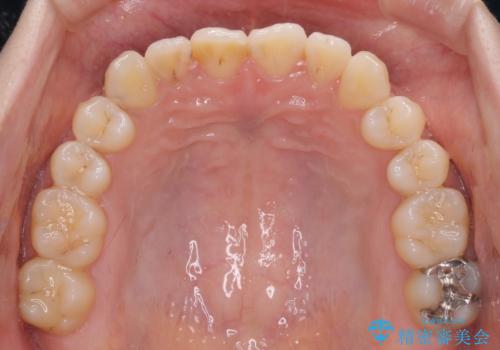

前歯のクロスバイトを治したい ワイヤー装置による矯正治療

- 前歯の反対咬合を気にして来院された患者様です。

クロスバイト改善まではスムーズに進みましたが、その後は強い舌の突出癖によりオープンバイトの期間が長く続きました。

舌のトレーニングをしっかりと実施してもらい、何とか仕上げることができました。